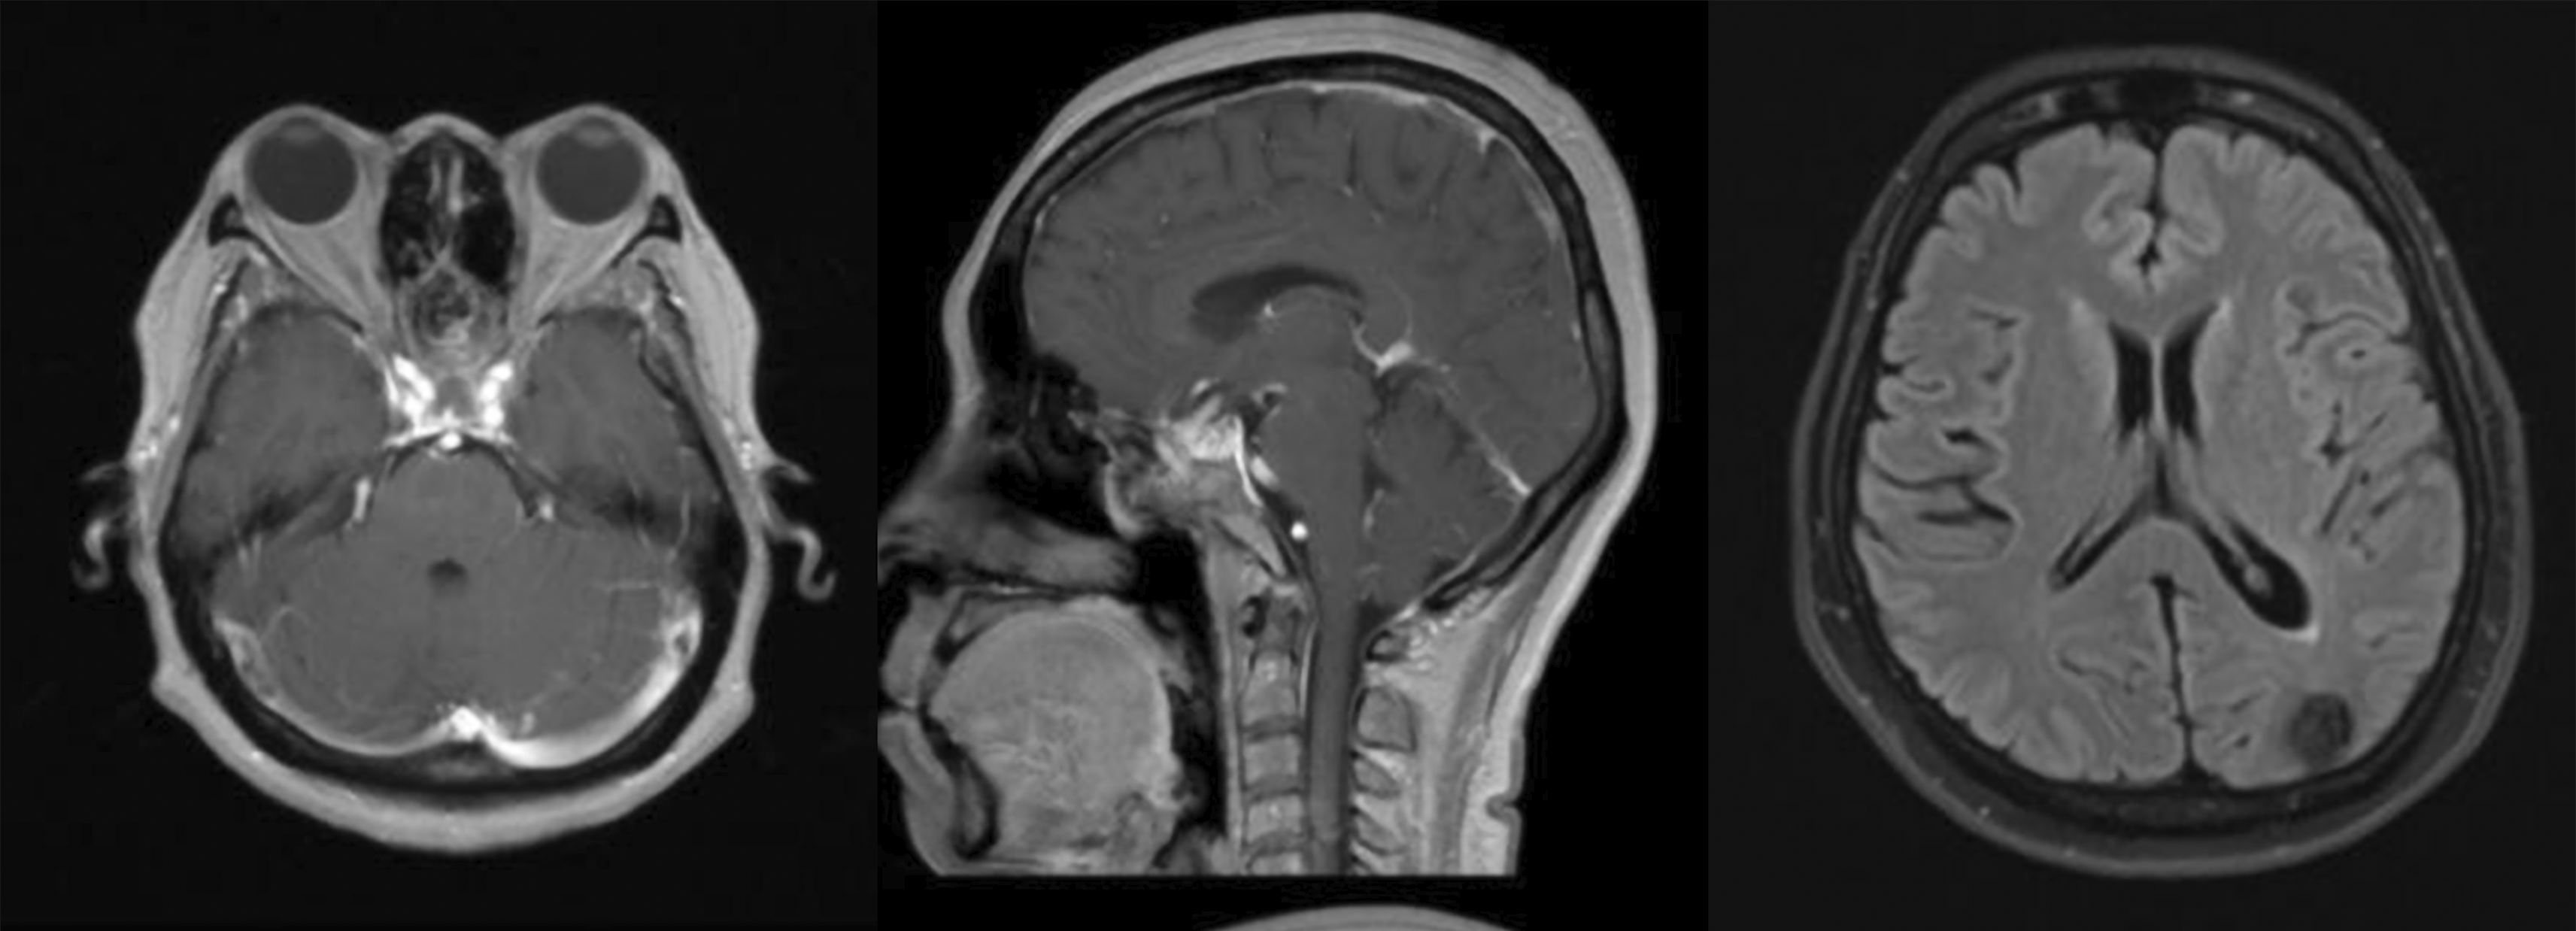

A 54-year-old female presented with a two-month history of progressively blurred vision and a right temporal hemianopia, superimposed on a two-year history of chronic headaches. Her medical history was negative for arterial hypertension, bleeding disorders or anticoagulant use. The timeline of the case presentation is shown in Figure 1. Hormonal status was within normal limit. Preoperative magnetic resonance imaging (MRI) revealed a 1.91 × 2.01 × 1.82 cm solid, globular mass that avidly enhanced with gadolinium and showed a dural tail attached to the tuberculum sella ( Figure 2). She underwent a Simpson Grade I resection of the tumour via a endoscopic endonasal transsphenoidal approach ( Figure 3). The surgery was unremarkable and histopathology confirmed a Meningothelial Meningioma, WHO Grade I. The immediate postoperative period (days one to four) was uneventful; the patient was conscious and alert with improving vision. The patient showed minimal CSF leakage from the nostril postoperatively and some polyuria adequately manage with desmopressin tablet 0.1 mg. However, on the postoperative day five, the patient was found to be drowsy (Glasgow Coma Scale score of 13).

A. Tuberculum on the anterior part of sellar floor was exposed and drilled. B. U shaped durotomy was performed exposing the tumor attached to the duramater. C. Tumor was being removed. Tumor was grayish red, easy to bleed with rubbery consistency and not suctionable. Detachment of tumor from surrounding sturctures. D. Neurovascular structures revealed including anterior communicating artery, Anterior cerebral artery (A1 and A2), recurrent artery of Heubner and Optic Nerve. There was no active bleeding seen after tumor removal.

Medical therapy to control intracranial pressure (ICP) was initiated, consisting of intravenous mannitol and head-of-bed elevation. Following this conservative management, her level of consciousness progressively improved over the next three days. However, the patient suddenly became aphasic and could not understand any command on day 13th postoperatively ( Figure 5). Another head CT scan was performed and revealed partially resolved ICH at the parietal lobe with slight additional thickness of subacute SDH and midline shift to the right. Conservative management with mannitol and tranexamic acid was continued. The patient showed clinical improvement after 2 days and discharged from hospital at day 18th postoperatively. The three-month postoperative MRI confirmed gross total resection of the meningioma and complete resolution of the remote haemorrhage, without evidence of any vascular malformation ( Figure 6).